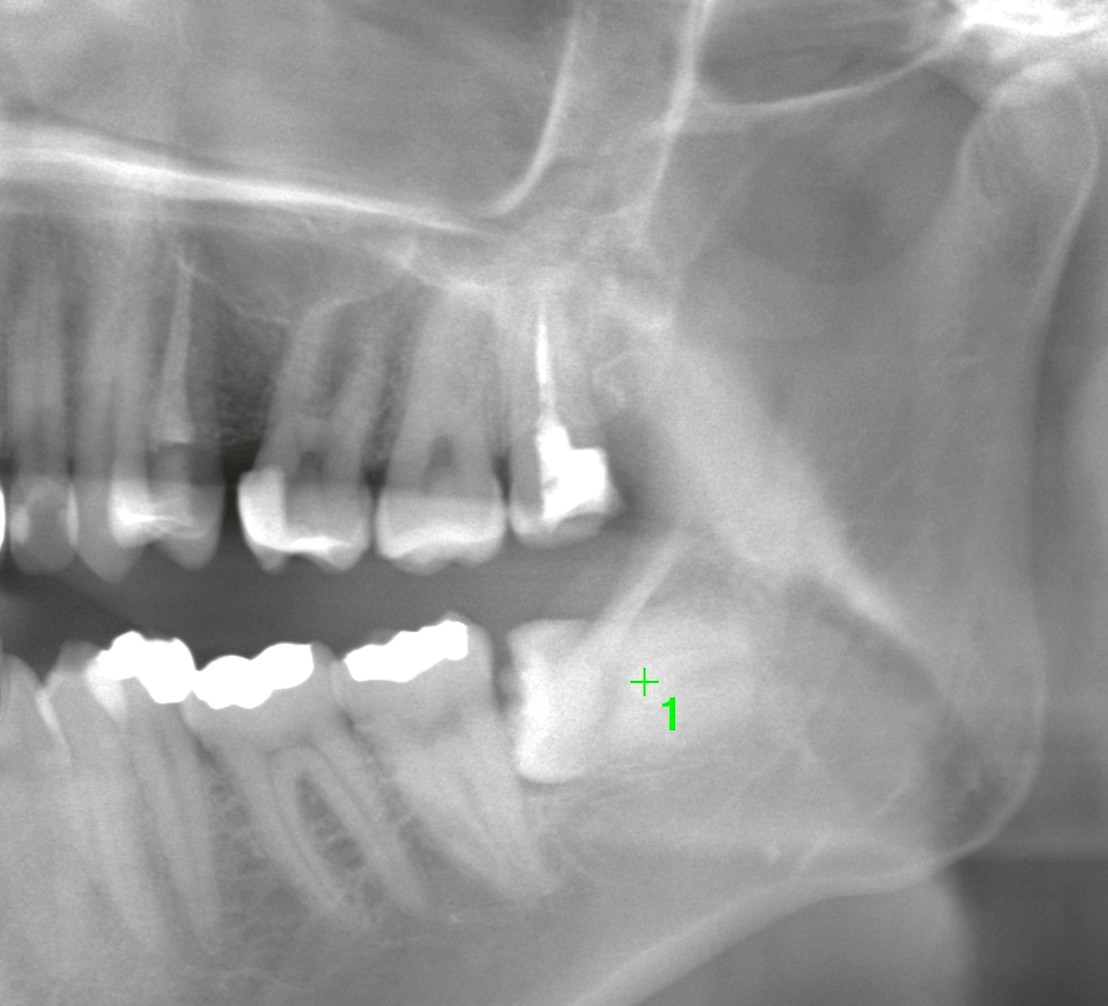

レントゲンで確認すると、下顎の親知らずは水平半埋伏。

この所見自体は、決して珍しいものではありません。

しかし今回のケースで、抜歯の難易度を大きく左右したのは

歯根が非常に長かったことでした。

今回のケースが難しかった理由

今回の患者さまは日本人でありながら、

例外的に歯根が非常に長いタイプでした。

この「歯根が長い」という要素が加わることで、

抜歯の難易度は一段階上がります。